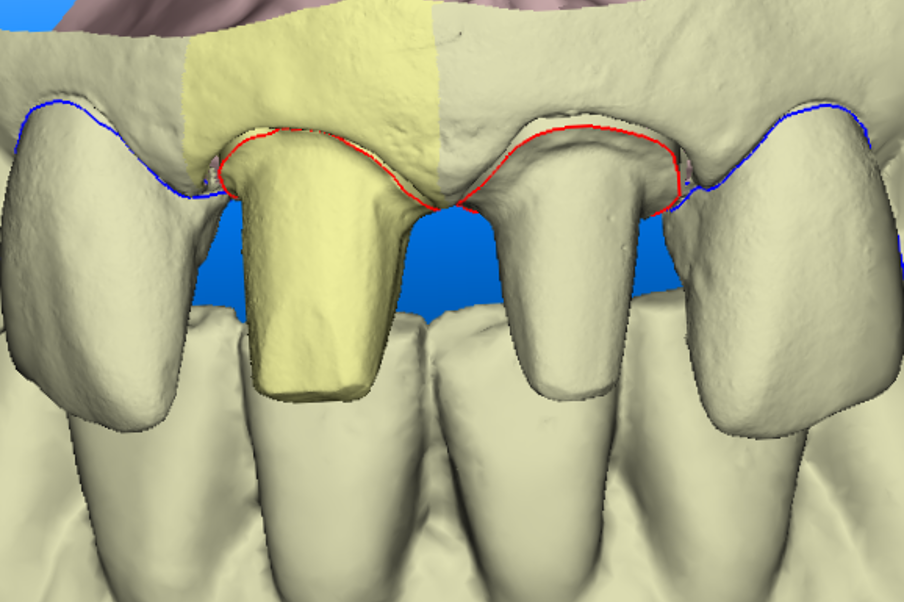

What happens if you have a case like the one below where you have preps and implants?

This is an example of a bigger case – one where we wanted to be able to incorporate the fixture position of the implants into the model.

To solve this puzzle, we had to use Kiwi ingenuity.

The closest translation of this New Zealand saying would be ‘thinking outside the box’.

As a result, the benefits we were seeing in our conventional workflows could also be applied to our implant cases.

You can see in the series of images below, courtesy of Ashley Bryne, how we did this.